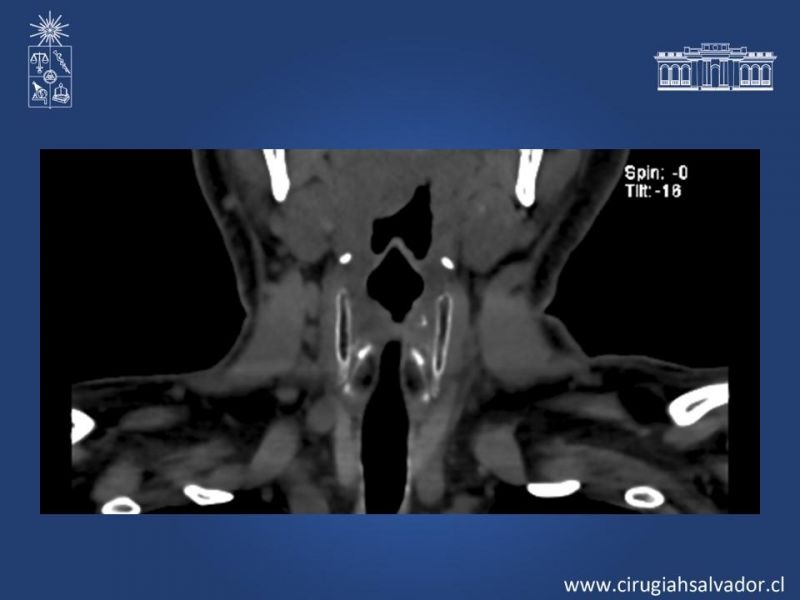

Stents de Vía Aérea

Cirugía Torácica

| Autor: Boris Marinkovic Gómez